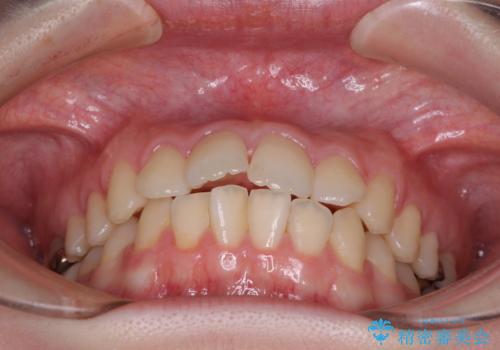

デコボコ歯列をきれいに インビザラインによる矯正治療

- 上下歯列全体のデコボコを気にして来院された患者様です。

主に下顎歯列全体の後方移動とIPR(歯と歯の間を削る)によってデコボコが解消するように設計し、インビザラインにより治療を行うこととしました。

1年半程度で終了するのではないかと予想しましたが、途中1年以上の来院がなく、トータルで3年の時間がかかってしまいました。

前歯のデコボコはより改善することが望ましい状態でしたが、患者様の希望により終了することとなりました。